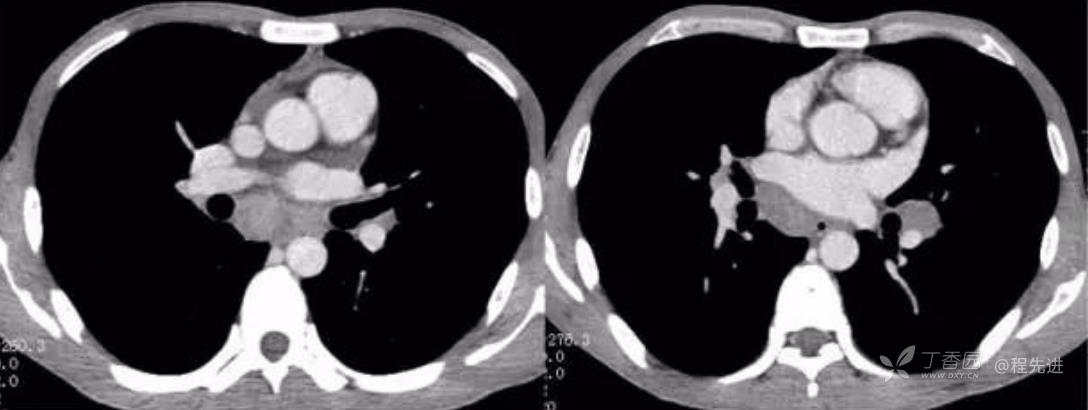

动脉期

静脉期

左动脉期,右静脉期